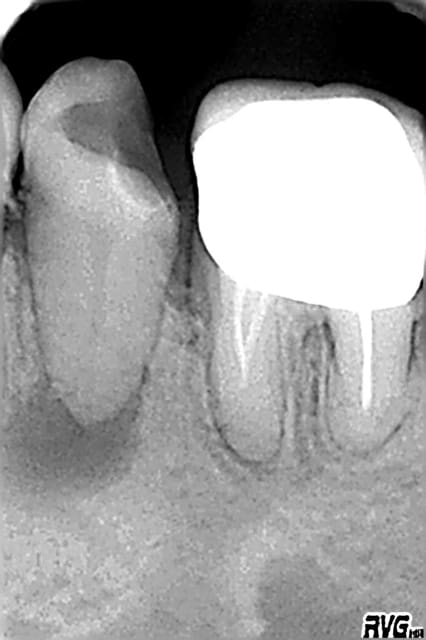

Curieusement je n'ai eu que 3 endos depuis, reprises sur 2 centrales et 1 reprise sur une 26.... 1 a été obturée et les 2 autres sont en cours (durailles les sagouines).

ps: steph comment tu géres la digue et la bague de cuivre.... j'ai dechiré 3 feuilles avant d'abandonner pour la molaire et donc j'ai partiellement desobturé cette fichue 26 mais pas "comme il le faudrait", et j'ai recommandé des boites de digue pasque du coup j'ai épuisé le stock.

ps j'ai bien localisé un mv2 "oublié" par mon predecesseur mais macache pour le cateteriser; comme il semble en continuité anatomique avec le mv1 (y'a comme une fissure qui joint les 2 entrées) j'espere qu'ils fusionnent plus haut car si lors de la prochaine seance je passe pas faudra essayer de noyer tout ça avec l'obturation du mv1.

Algi

La bague de cuivre ne sert en fait que de matrice a ton materiau de reconstitution.

Sur la radio que tu montres, il me semble que c'est vide a l'interieur.

Une fois que tu a fais ta reconstitution il suffit de chanfreiner les bords occlusaux du moignon afind d'eviter qu';il ne soit coupants et ne dechirent la digue quand elle passe.

Autre astuce, bien libérer les points de contact avec les dents adjacentes pour laisser paser lel champ operatoire.

C'est deja un bon point d'essayer ;-)